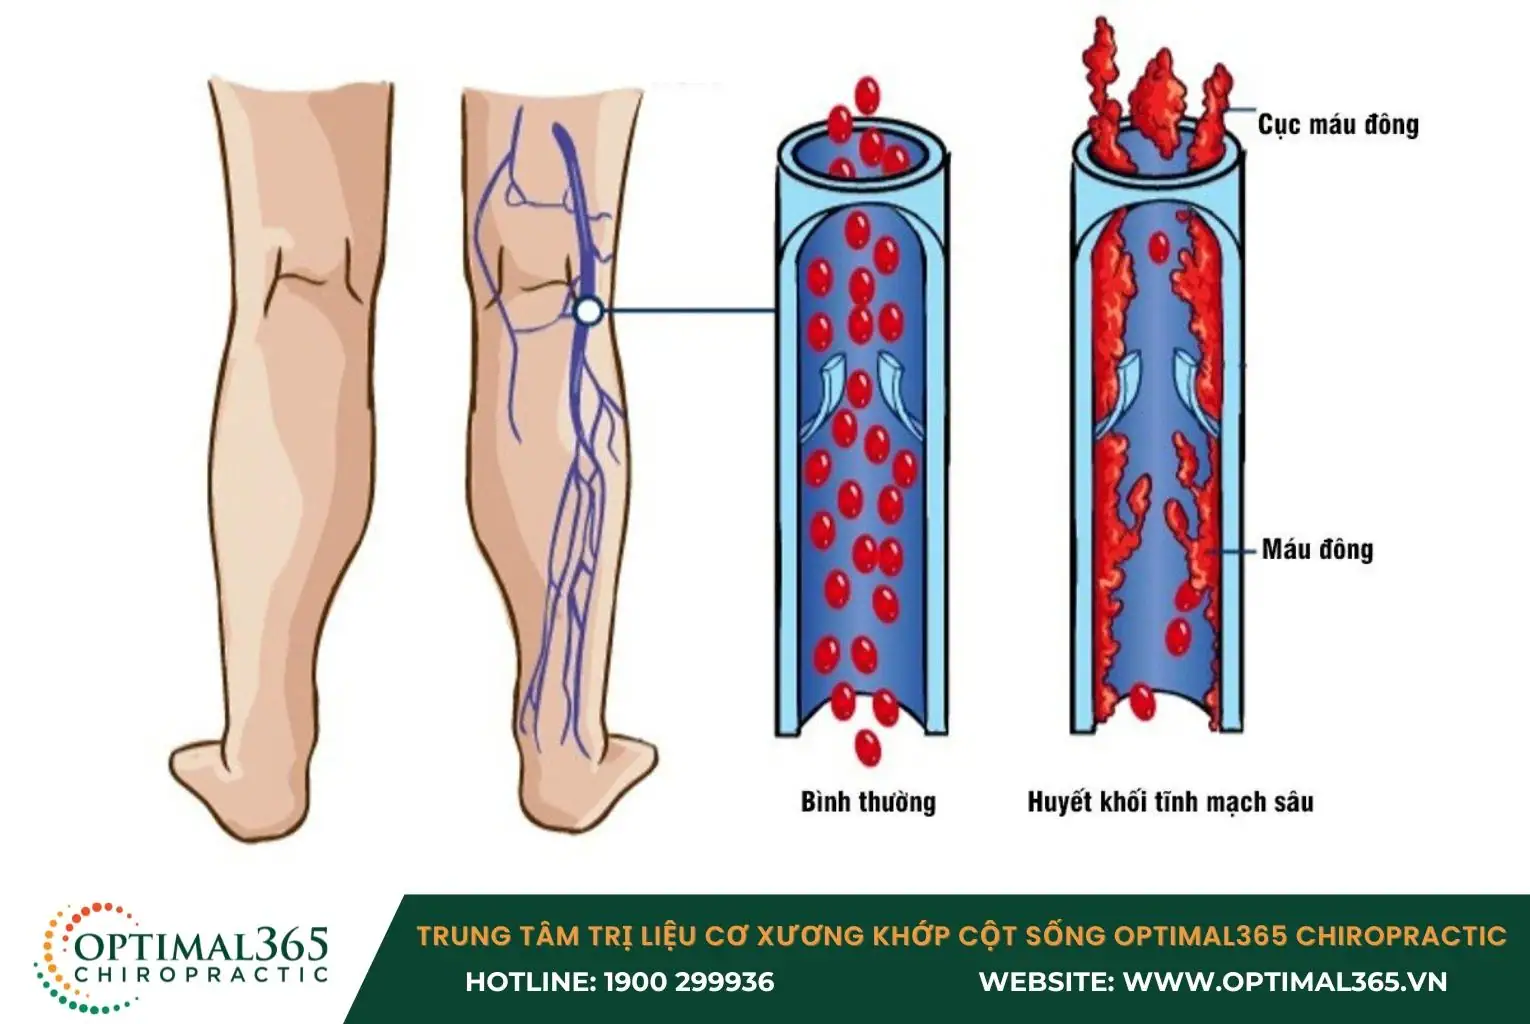

- Huyết khối tĩnh mạch sâu (DVT)

Huyết khối tĩnh mạch sâu (DVT) xảy ra khi các cục máu đông xuất hiện trong các tĩnh mạch sâu ở cánh tay hoặc chân. Tình trạng này làm cho máu không thể lưu thông bình thường, dẫn đến hiện tượng đau nhức ở các cơ tay và bắp chân.

Mặt khác, đau bắp chân có thể là dấu hiệu cảnh báo các vấn đề sức khỏe nghiêm trọng hơn, chẳng hạn như huyết khối tĩnh mạch sâu (DVT) hoặc suy tĩnh mạch mạn tính. Đây đều là những tình trạng tiềm ẩn nguy cơ biến chứng cao nếu không được điều trị kịp thời. Đặc biệt, nếu kèm theo các triệu chứng như sưng phù, da đổi màu, hoặc khó thở cần phải đi thăm khám ngay lập tức.